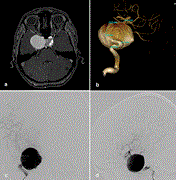

Giant internal carotid aneurysm: endovascular parent artery occlusion after failed treatment using a flow diverter—case report

Dalibor Sila and others

Journal of Surgical Case Reports, Volume 2021, Issue 2, February 2021, rjab015, https://doi.org/10.1093/jscr/rjab015